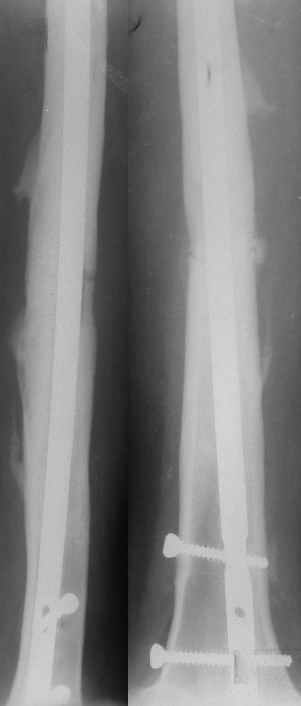

История болезни этой пациентки началась 5 лет назад с перелома бедра в ДТП, оперирована 2-ы пластиной накостно в одной из больниц нашего города, 2-ы перелом импланта, после последнего раза поступила в нашу клинику, где был выполнен блокированный остеосинтез. Через два года гвоздь удалён (по просьбе больной), Rg-сращение. Через год после удаления рефрактура от незначительной травмы, остеосинтез гвоздём с блок., в раннем послеоперац. периоде жировая эмболия, после купирования амбул. лечение. Прошу советов по дальнейшему лечению.

рефрактура через год после удаления штифта

через мес. после последнего остеосинтеза